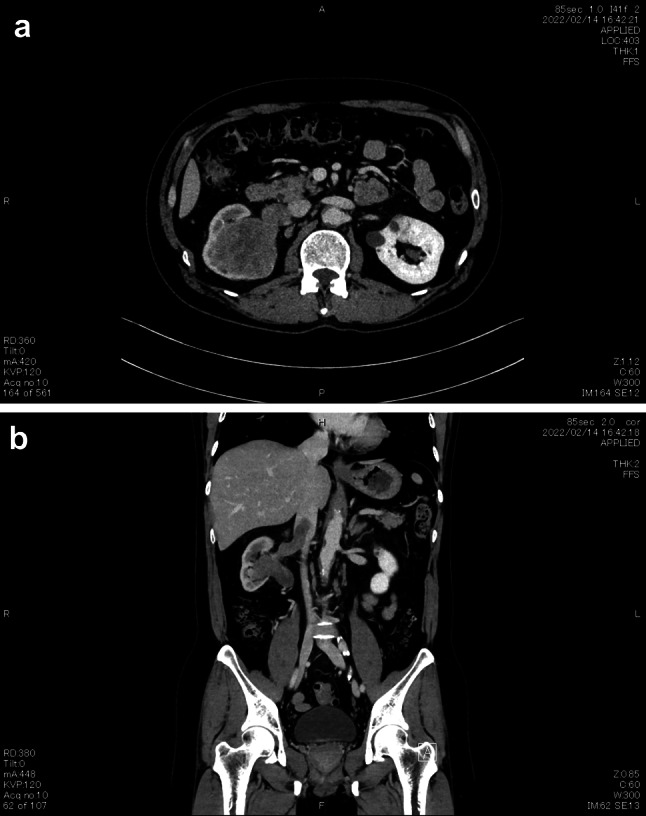

我们在此介绍一位并发下腔静脉瘤栓的肉瘤型肾细胞癌患者,我们用尼伐单抗加伊匹单抗进行了治疗。治疗的结果是肿瘤缩小,从而能够通过机器人辅助腹腔镜根治性肾切除术完全切除肿瘤。患者目前仍健在,没有复发迹象。

We here present a patient with a sarcomatoid renal cell carcinoma complicated by inferior vena cava tumor thrombus that we treated with nivolumab plus ipilimumab. This resulted in shrinkage of the tumor, enabling complete resection by robot-assisted laparoscopic radical nephrectomy. The patient is still alive with no evidence of recurrence.